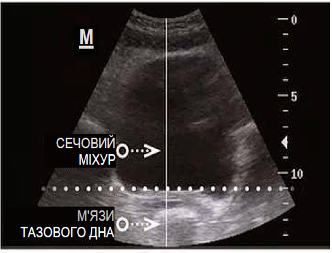

ДО

Вихідні порушення:

ПІСЛЯ

Механізм лікувальної дії: